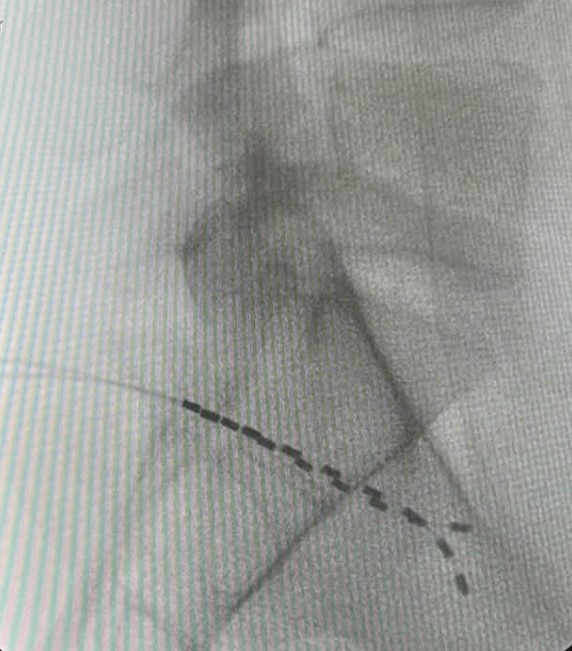

Ποια είναι η θεραπευτική διαδικασία

Η τεχνική της διέγερσης του DRG είναι σχεδόν πανομοιότυπη με τη τεχνική διέγερσης του νωτιαίου μυελού. Ωστόσο, στόχο της νευροδιέγερσης εδώ αποτελεί το συγκεκριμένο γάγγλιο και όχι ο νωτιαίος μυελός. Τα γάγγλια της ραχιαίας ρίζας βρίσκονται στα μεσοσπονδύλια τρήματα.

Η διέγερση του DRG αφορά στην εμφύτευση ηλεκτροδίου που στέλνει ηλεκτρικά ερεθίσματα στη συγκεκριμένη περιοχή. Οι ώσεις αυτές διακόπτουν τη μετάδοση των σημάτων πόνου από το περιφερικό προς το κεντρικό νευρικό νευρικό σύστημα. Με απλά λόγια, η διέγερση του γαγγλίου τροποποιεί την αντίληψη του πόνου. Πριν την τελική εμφύτευση του ή των ηλεκτροδίων και τη σύνδεση αυτών με τη γεννήτρια, προηγείται διάστημα δοκιμαστικής διέγερσης με φορητή, εξωτερική γεννήτρια.